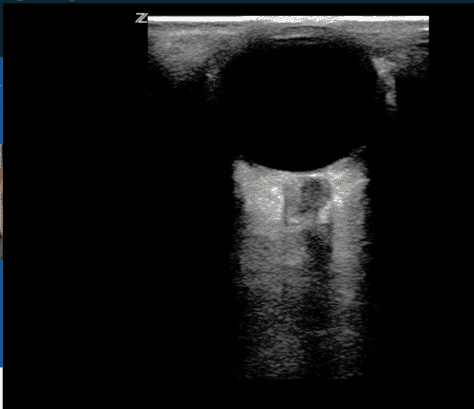

- Маніпулюйте датчиком, доки нерв і його оболонка не стануть видимими внизу екрана. Приклад правильного ультразвукового зображення оболонки зорового нерва можна побачити на Зображенні 2.

- Використовуючи опцію вимірювання на пристрої, відміряйте 3 мм вглиб від диска зорового нерва, а потім виконайте друге вимірювання перпендикулярно до першого. Друге вимірювання має охоплювати горизонтальну ширину оболонки зорового нерва (Зображення 2). Патологічне значення ONSD показане на Зображенні 3.

Ультразвукове зображення ока та оболонки зорового нерва у нормі

Щоб виміряти ONSD, наведіть ультразвуковий датчик на диск зорового нерва та відміряйте 3 мм вглиб від диска вздовж ходу зорового нерва. Друге, перпендикулярне, вимірювання проводиться в попередньо визначеній точці та становить горизонтальну ширину оболонки зорового нерва. На цьому зображенні ONSD було визначено як 5,1 мм, що є нормою.

Діаметр оболонки зорового нерва становив 6,8 мм. Згодом було підтверджено підвищення ВЧТ (26 мм рт.ст.) після встановлення внутрішньокраніального датчика для моніторингу ВЧТ.